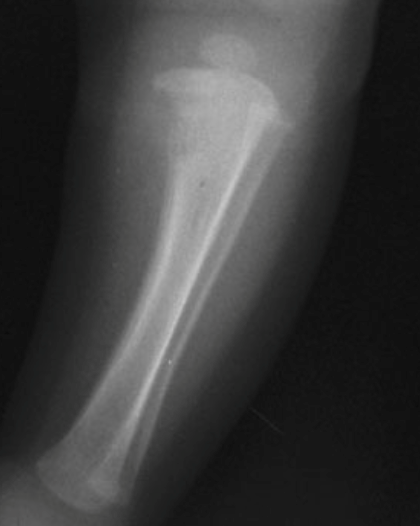

Na sífilis congênita precoce (diagnóstico antes dos 2 anos de idade) ocorre caracteristicamente uma metafisite e o acometimento simétrico de múltiplos ossos. Observa-se um alargamento da metáfise e as epífises são poupadas. Com a fragilidade óssea, é comum a ocorrência de fraturas patológicas. Um achado clínico nessa fase é a pseudoparalisia dos membros, a pseudoparalisia de Parrot, que é decorrente da metafisite e não de uma alteração neurológica ou muscular. O sinal de Wimberger é um sinal radiológico característico da sífilis congênita e é evidenciado pela destruição medial da metáfise proximal da tíbia (FIGURA 2).

FIGURA 2. Sinal de Wimberger, Lesão na metáfise medial da tibia.